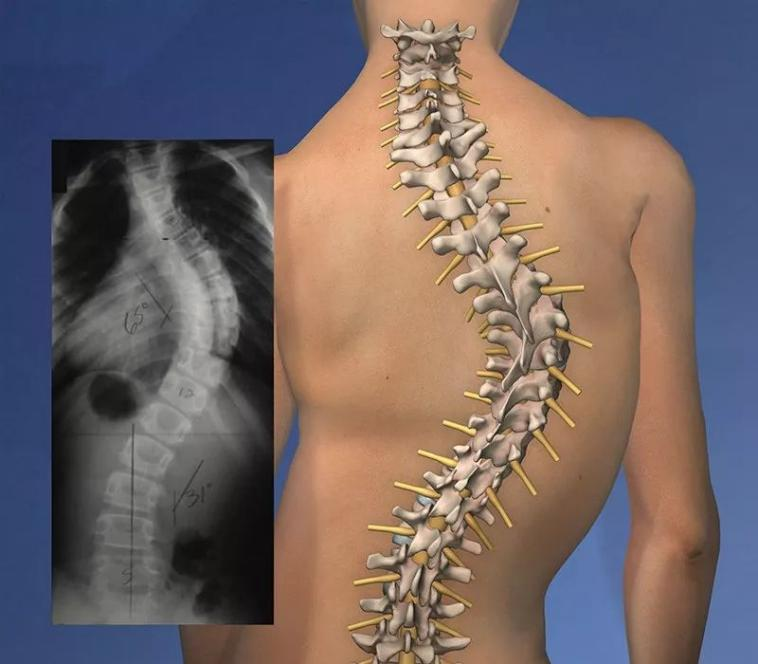

一、什么是脊柱侧弯 ?

通俗来讲,就是脊柱“长歪了”,处于三维畸形状态。国际脊柱侧弯研究学会对脊柱侧弯定义为:如果Cobb角大于10度则定义为脊柱侧弯。